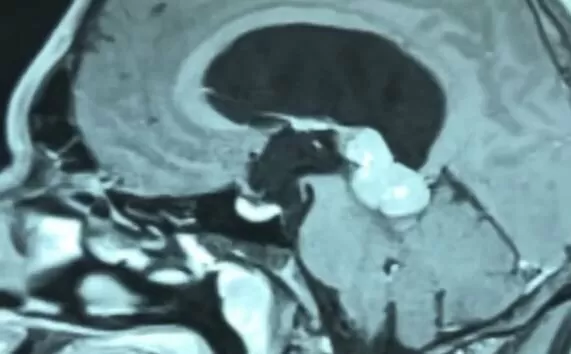

Diagnosis involves CT and/or MRI of the brain with contrast.